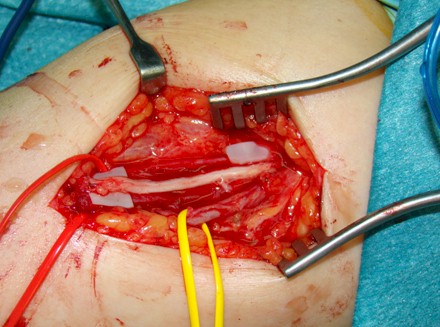

Figura 2: Exposición quirúrgica de la lesión

Bajo bloqueo del plexo braquial e isquemia se realizó una incisión cutánea en “S” alargada sobre el eje mayor del tumor, disección subcutánea y exposición de la lesión envuelta en su cápsula. Con gafas lupa y material microquirúrgico se llevó a cabo la enucleación intracapsular del tumor, tras la disección cuidadosa del resto de fascículos nerviosos no afectos (figuras 2 y 3).